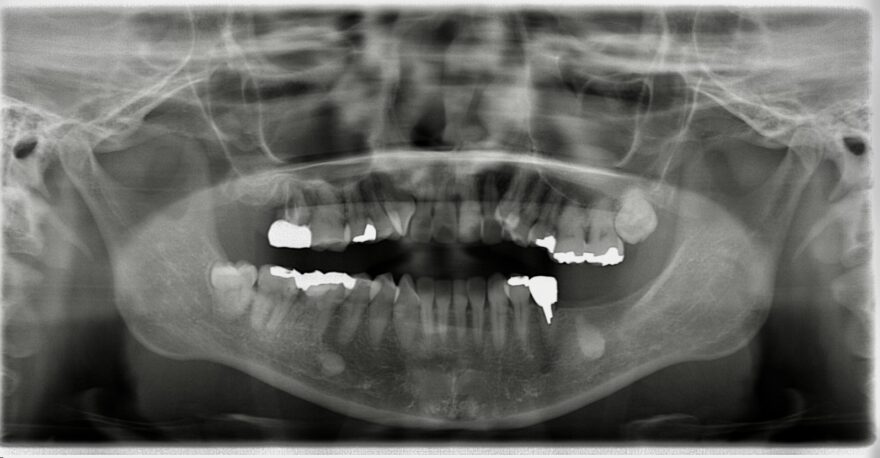

初診時のレントゲン写真

左下の奥歯が崩壊しています。

右下の奥歯を失い、噛み合わせが歪んでいることが分かります。

右上の八重歯が気になります。